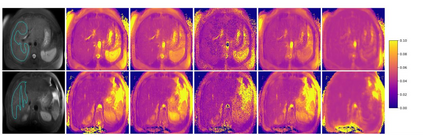

$T_{1\rho}$ mapping is a promising quantitative MRI technique for the non-invasive assessment of tissue properties. Learning-based approaches can map $T_{1\rho}$ from a reduced number of $T_{1\rho}$ weighted images, but requires significant amounts of high quality training data. Moreover, existing methods do not provide the confidence level of the $T_{1\rho}$ estimation. To address these problems, we proposed a self-supervised learning neural network that learns a $T_{1\rho}$ mapping using the relaxation constraint in the learning process. Epistemic uncertainty and aleatoric uncertainty are modelled for the $T_{1\rho}$ quantification network to provide a Bayesian confidence estimation of the $T_{1\rho}$ mapping. The uncertainty estimation can also regularize the model to prevent it from learning imperfect data. We conducted experiments on $T_{1\rho}$ data collected from 52 patients with non-alcoholic fatty liver disease. The results showed that our method outperformed the existing methods for $T_{1\rho}$ quantification of the liver using as few as two $T_{1\rho}$-weighted images. Our uncertainty estimation provided a feasible way of modelling the confidence of the self-supervised learning based $T_{1\rho}$ estimation, which is consistent with the reality in liver $T_{1\rho}$ imaging.